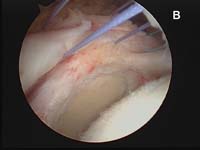

For the most common type of rotator cuff tears, the tendon of the rotator cuff muscle called the supraspinatus will have torn and pulled back slightly from its normal attachment at the greater tuberosity atop the humerus. These smaller tears which are "non-retracted" or "minimally-retracted" only need to be freshened or débrided back to stable, healthy tendon tissue, then mobilized back to the tuberosity and fixed in place. (See Fig. 9) When using an all arthroscopic technique, the surgeon will employ special devices called "suture anchors" to hold the tear in position when it heals. These "anchors" can be made of metal or absorbable compounds. They are screwed or pressed into the bone of the attachment site and the attached sutures are used to tie the edge of the rotator cuff in place.

As tears become larger, they deform and the tendon tissue "shrinks". Thus, larger tears need to be refashioned, repaired side-to-side, or "zipped" closed using a technique called margin convergence. This technique is analogous to zippering shut an open tent flap. The rotator cuff tissue is freed from a scarred, retracted position and repaired side-to-side to ‘close the tent flap’ and restore the tissue over the top of the humeral head. (See Fig.4 and Fig.10) The repaired cuff tissue is then fixed to the site it originally tore away from using specially-designed implants called suture anchors. These are metallic or absorbable plastic devices that secure sutures to the bony attachment. The sutures are then sewn through the torn edge of the cuff to complete the repair.